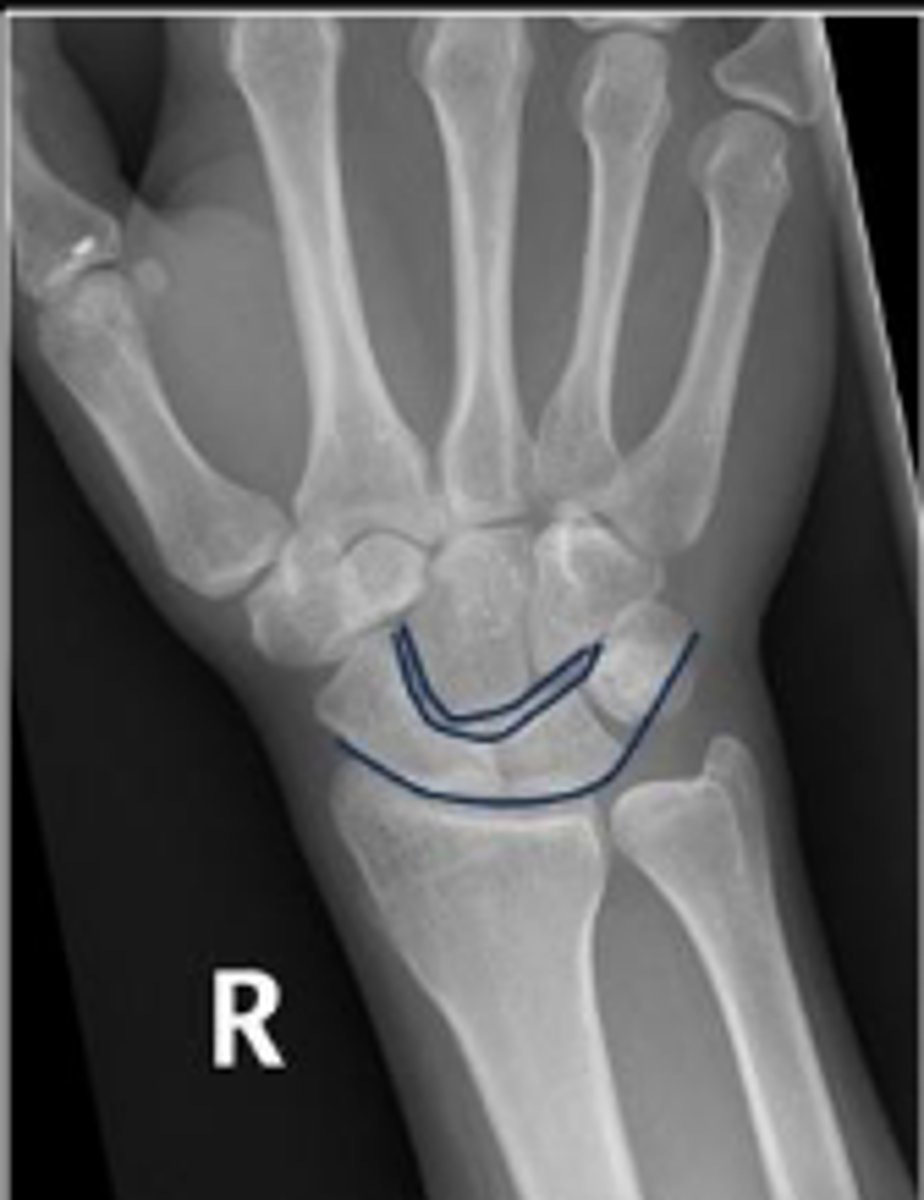

3 arcs of carpal alignment

What is the name of the assessment

Proximal cortical aspect of the first (proximal)

carpal row (ARC 1)

What are the landmarks for the most proximal line in the assessment?

Distal cortical aspect of the first (proximal) carpal

row (ARC 2)

What are the landmarks for the most middle line in the assessment?

Proximal cortical aspect of the second (distal)

carpal row (ARC 3)

What are the landmarks for the most distal line in the assessment?

SLAC wrist; carpal dislocation, carpal fracture

Name 2 conditions that will result in an alteration of the assessment?